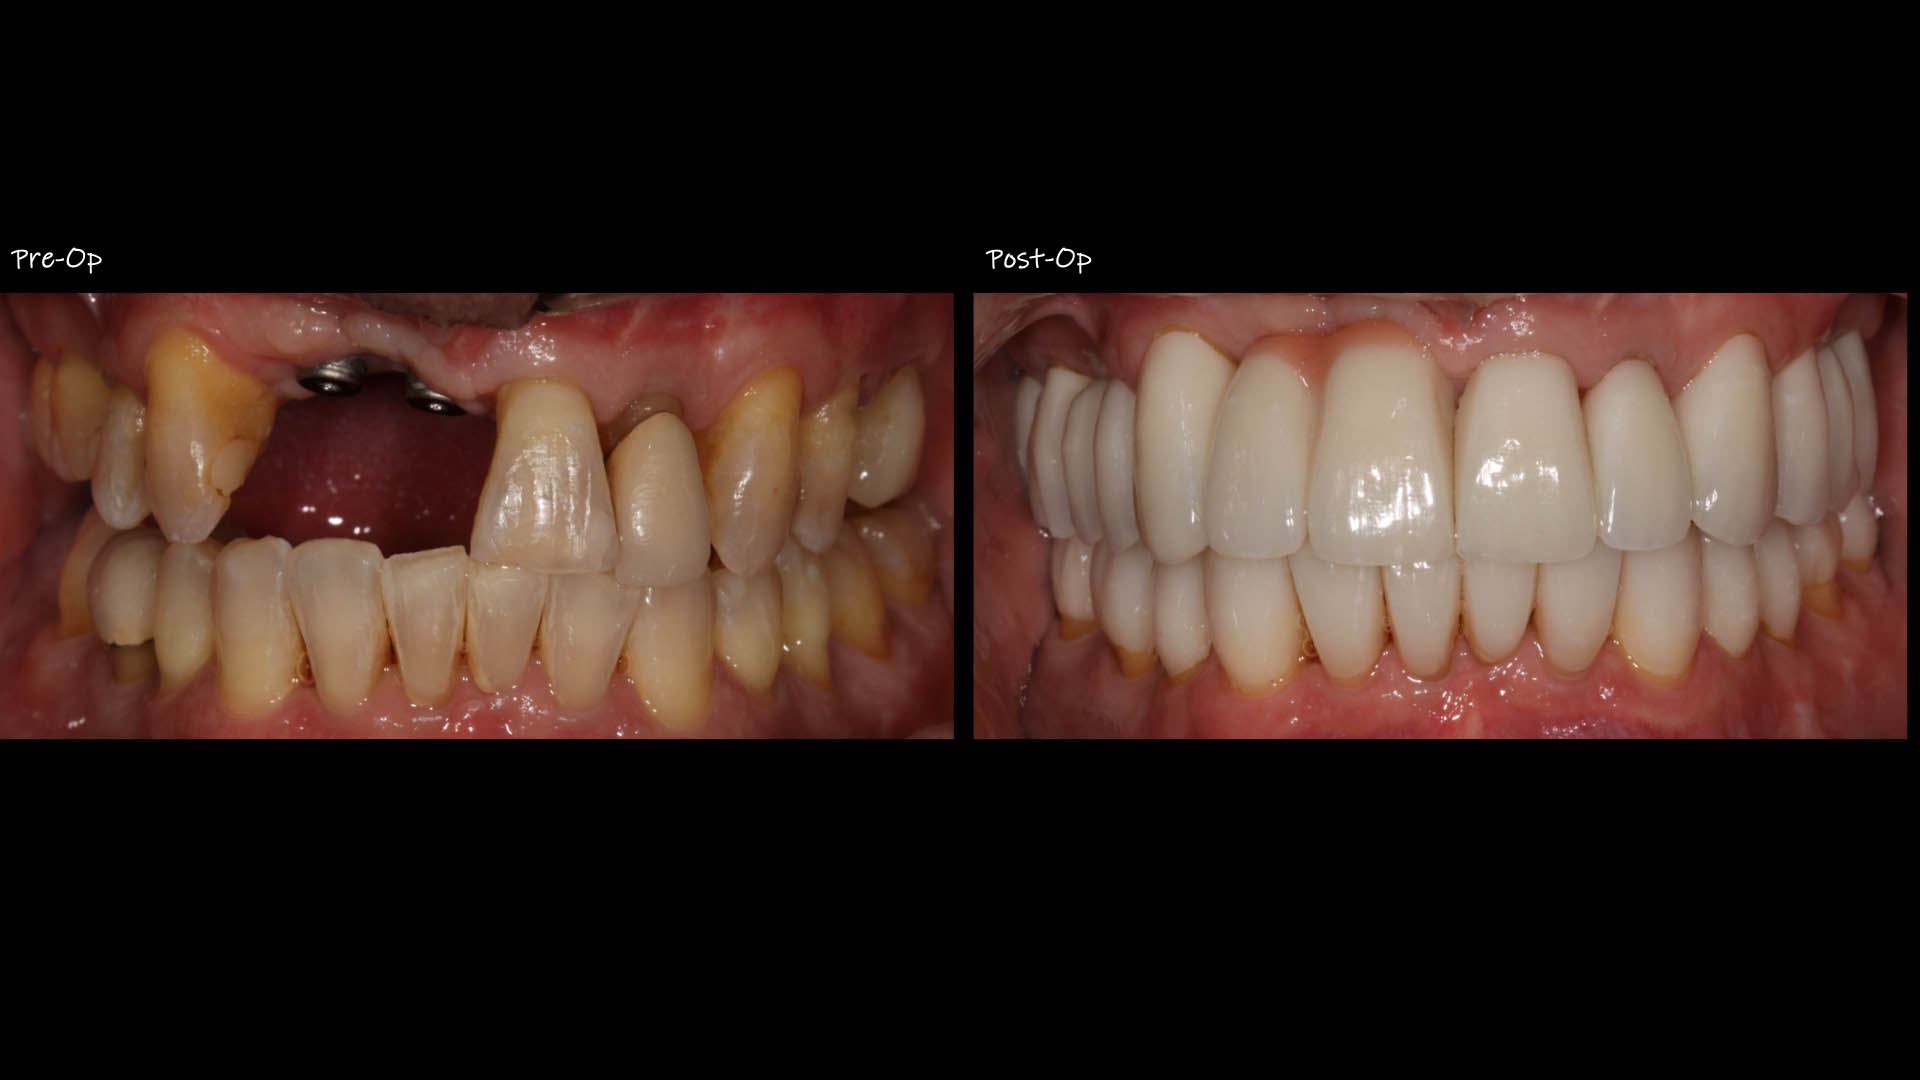

Take a glimpse into the magic of Coral Gables Dentistry through our before and after pictures. See firsthand the incredible smile makeover transformations that have brought confidence and joy to our patients.